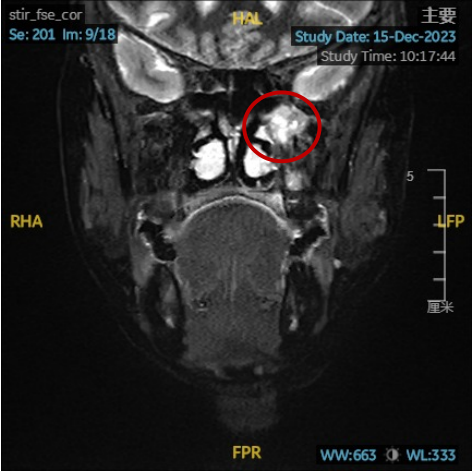

术前